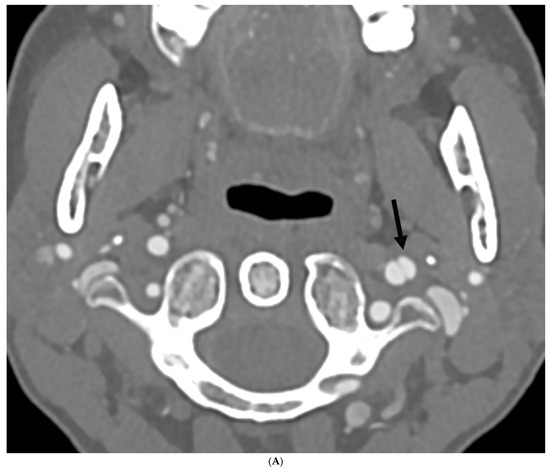

Prevalence of Intracranial and Cervical Artery Abnormalities in Patients with Hypermobile Ehlers–Danlos Syndrome and Hypermobility Spectrum Disorders Presenting to an Academic Headache Clinic

by Todd D. Rozen, Katelyn A. Bruno, Ethan M. Rozen, Frances C. Wilson, Marysia S. Tweet, Raymond C. Shields, Sharonne N. Hayes, Dacre R. T. Knight, Shilpa N. Gajarawala, Sukhwinder J. S. Sandhu, Alok A. Bhatt and DeLisa Fairweather

Neurol. Int. 2026, 18(2), 33; https://doi.org/10.3390/neurolint18020033 - 11 Feb 2026

Background/Objective: It remains unknown whether patients with the more common forms of hypermobility carry an elevated risk for the development of intracranial/cervical artery abnormalities. The objective of this study was to determine the prevalence of unruptured intracranial aneurysms, spontaneous cervical artery dissections, and fibromuscular dysplasia in patients with hypermobile Ehlers–Danlos Syndrome (hEDS) and hypermobility spectrum disorders (HSD) who presented to an academic headache clinic. Methods: This is a retrospective cohort study. We used an electronic medical record to look for all patients seen at the Mayo Clinic Florida Headache Center and EDS Clinic between 2019 and 2025 with a diagnosis of hEDS or HSD and neuroimaging of both the intracranial and cervical arteries. Results: There were 103 patients who met the inclusion criteria. There was no statistically significant difference between hEDS and HSD patients in developing cerebral/cervical arterial anomalies. Of the sample, 95% of the hypermobile patients with abnormal neuroimaging also had migraine. A total of eleven (10.7%) patients (hEDS + HSD) were diagnosed with unruptured intracranial aneurysms. Trends included age less than 50 years, small aneurysms in the anterior circulation, and having migraine with aura. Five (4.8%) patients were diagnosed with spontaneous cervical artery dissection with trends for HSD, over the age of 50 years, vertebral artery involvement and a history of migraine without aura. Six (5.8%) patients were diagnosed with fibromuscular dysplasia with trends for HSD, over the age of 50 years, carotid artery involvement and a history of migraine with aura. Conclusions: This is the first study to identify that patients with the more common type of EDS, HSD and hEDS, and a possible concomitant history of migraine have a heightened risk for the development of unruptured intracranial aneurysms, spontaneous cervical artery dissections, and fibromuscular dysplasia. Our findings suggest the need for targeted screening with intracranial and extracranial arterial imaging for this unique patient population. Full article